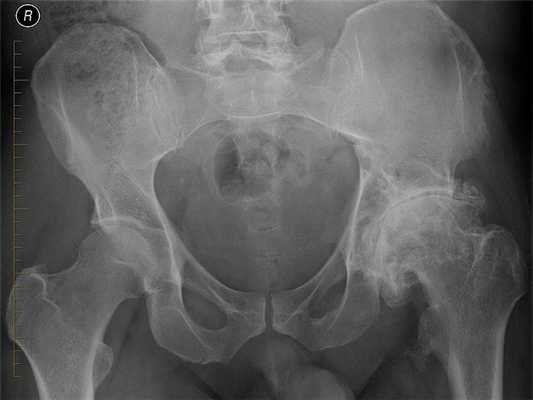

В группу системных заболеваний включены патологии, поражающие несколько суставов, провоцирующие развитие в них воспалительного процесса. Сначала разрушаются хрящи, что приводит к нестабильности сочленений, а затем деформируются и костные структуры. Системные заболевания обычно бывают аутоиммунными. Они возникают из-за неадекватного ответа иммунной системы на проникновение в организм инфекционных возбудителей. К ним относятся:

- анкилозирующий спондилоартроз;

- ревматоидный артрит;

Основными причинами деформирующего артроза тазобедренного сустава становятся различные травмы и заболевания. Патология чаще всего диагностируется у людей старше 40 лет. Она прогрессирует постепенно, проявляясь болями при ходьбе, утренней отечностью и скованностью движений. Деформирующий артроз 1-2 степени тяжести хорошо поддается консервативному лечению. А при значительной деформации костей пациентам показано хирургическое вмешательство.

Деформирующий артроз тазобедренного сустава (ТБС) — дегенеративно-дистрофическая патология, сначала поражающая хрящ. Из-за нарушения питания он становится шероховатым, менее упругим, а на его поверхности появляются трещины. Теперь подвздошная и бедренная кости не плавно скользят, а с трудом смещаются относительно друг друга. Это приводит к еще большему повреждению хрящевой прокладки сустава.

Вскоре кости не выдерживают повышенных нагрузок и деформируются. Образуются костные наросты — остеофиты. Смещаясь, они травмируют мягкие ткани, ущемляют кровеносные сосуды, нервные окончания.

Степень артроза ТБС определяется характером и выраженностью симптомов. Наиболее часто клиническая картина соответствует определенной стадии патологии, которая устанавливается с помощью рентгенографии. Чем серьезнее повреждены хрящевые и костные структуры, тем интенсивнее боли и скованность движений.